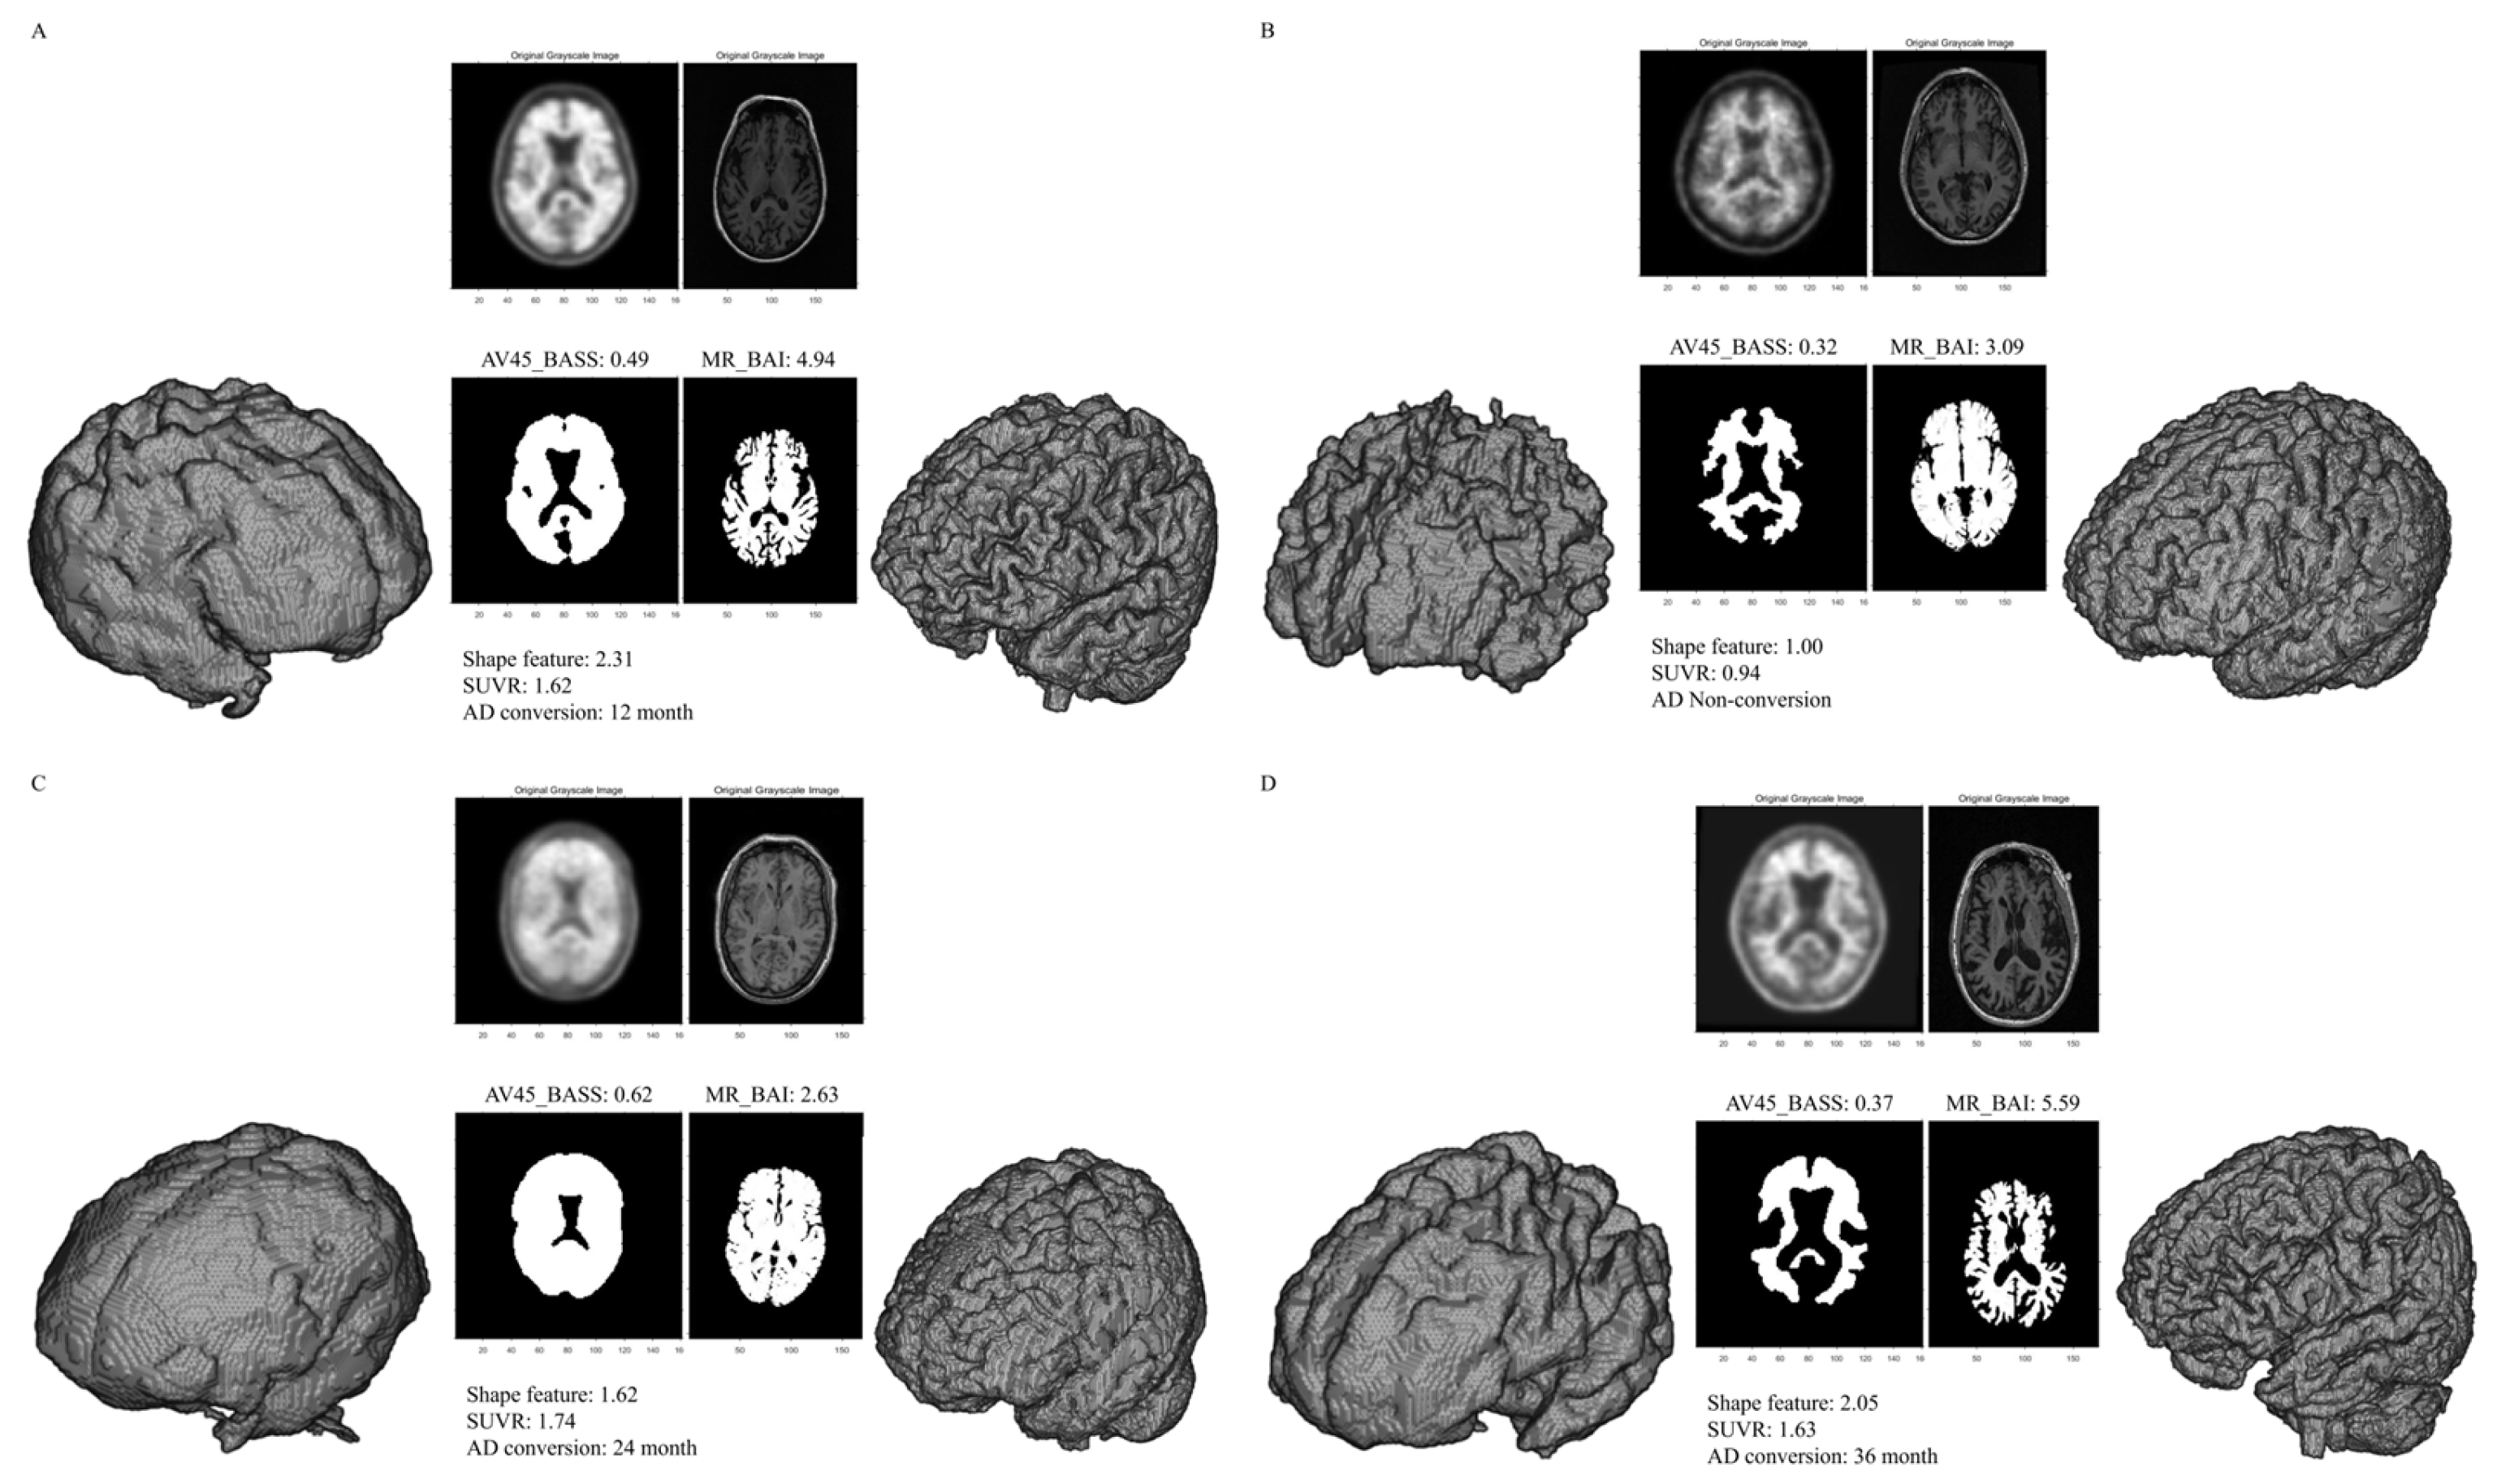

Figure 1.

Representative segmentations used to measure the BASS and BAI. The volume of interest (VOI) from a patient with conversion to AD showed a smooth surface on AV-45 PET (high BASS score) and an irregular surface on brain MRI (high BAI score) (A). The VOI from a patient without conversion to AD showed a sharp surface on AV-45 PET (low BASS score) and a regular surface on brain MRI (low BAI score) (B). The VOI from a patient with conversion to AD showing a smooth surface on AV-45 PET (high BASS score) and a regular surface on brain MRI (low BAI score) (C). The VOI from a patient with conversion to AD showed a sharp surface on AV-45 PET (low BASS score) and an irregular surface on brain MRI (high BAI score) (D). Abbreviations: BASS, brain amyloid smoothing score; BAI, brain atrophic index; AV-45, F-18 florbetapir; SUVR, standardized uptake value ratio; AD, Alzheimer’s disease.

3.2. Imaging Parameters

The mean SUVR, AV45_BASS, MR_BAI, and shape feature values were 1.22 ± 0.23, 0.40 ± 0.07, 3.98 ± 0.54, and 1.59 ± 0.33, respectively. Representative SUVR, AV45_BASS, MR_BAI, and shape feature examples are presented in Figure 1. SUVR, AV45_BASS, MR_BAI, and shape feature values were significantly higher in converters than in non-converters. The imaging parameters used in the 334 patients included in this study are summarized in Table 1.